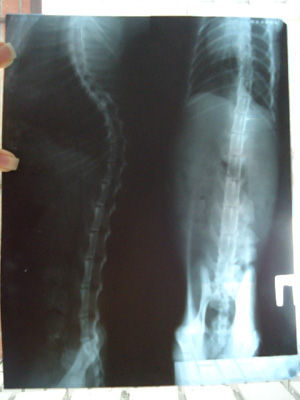

Ренген и анализы: Не очень четко видно. По биохимии очень большая амилаза.